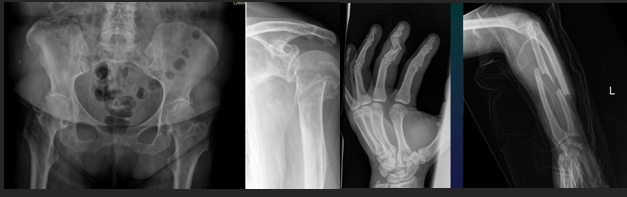

MSK Trauma Rof of Imaging

Positive Dg + lesion type

Monitoring + Dg complications

METHODS

CT (complex fractures)

Conventional Xray

Nuclear Medecine (sometimes)

Arthrography

Angiography (concomitant vascular involvement)

MRI (soft tissue, bone concussion)

Knee

Gonarthrosis

Hip

Coxarthrosis

Hand

Polyarthrosis (DIPh, Trapezo MC1)

Arthrosis Rx

GENERAL Rx signs

Joint space narrowing (even or uneven)

Subchondral OS

Subchondral cysts

Osteophytes

Technique: 2 views AP + prophyle